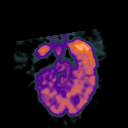

Glioma Overlay -- Slice #6

[Home][Help][Clinical] Slice 6